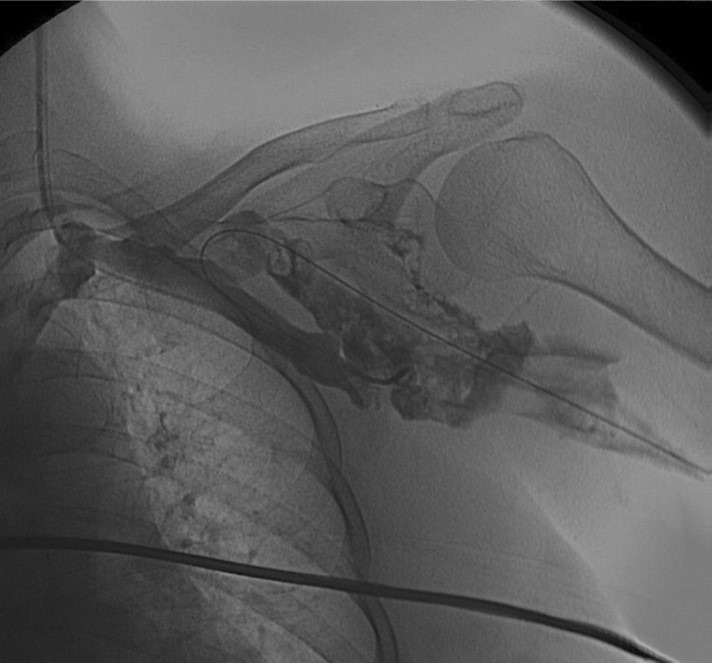

Retrograde venogram을 시행하면서 left basilic vein을 찾아 두 개의 7mm balloon(synergy, Boston, Ireland)을 사용하여 occlusion 된 vein 에 대한 Criss-Cross “double-balloon” angioplasty를 시행하였다(Fig. 6) .

Fig. 6.

Criss-Cross “double-balloon” technique in left basilic van